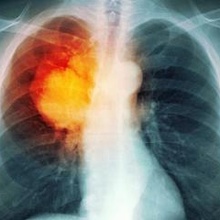

Новая технология позволит диагностировать рак легких на ранней стадии

Возможность диагностики немелкоклеточной карциномы на ранней стадии существенно снизит показатели смертности.